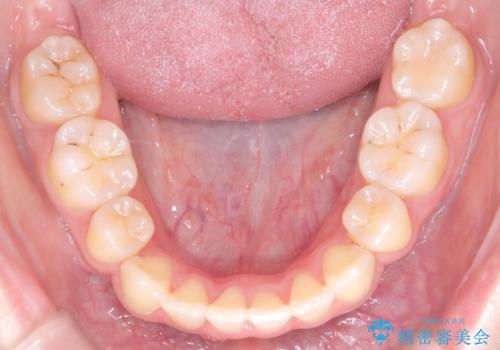

- 患者様は、結婚式までに歯並びを整えたいとのご要望で来院されました。診断の結果、上下左右の第一小臼歯を抜歯し、歯列全体を整える計画としました。審美性を重視し、目立ちにくいホワイトワイヤーを使用した矯正を提案しました。治療期間は2年を目安とし、結婚式までに前歯の整列と噛み合わせを優先的に整えるスケジュールで進めました。定期的な調整と経過観察を通じて、計画的に治療を進めました。

結婚式までに仕上げるため、通常よりも細かく調整を行い、歯の動きを効率的に管理しました。審美ワイヤーを使用したことで、治療中も目立ちにくく、写真撮影などの日常生活での見た目の負担を軽減しました。抜歯部分のスペースを閉じる際には、前歯の位置や噛み合わせのバランスに配慮し、過度な力がかからないよう進めました。患者様の大切なイベントに間に合うよう治療計画を立て、理想的な仕上がりを実現しました。